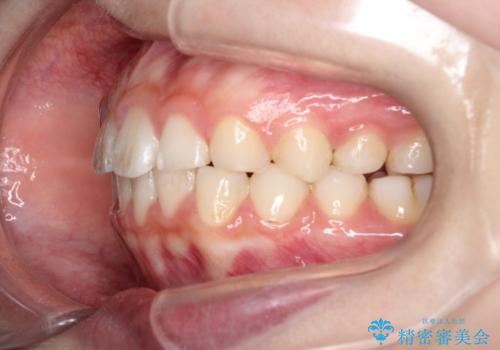

【インビザライン】出っ歯を引っ込めたい。

- 前歯の隙間と、出っ歯に見えることを主訴に来院されました。

できるだけ目立たない装置をご希望されましたので、インビザラインにて治療を行いました。

治療中は、できるだけ前歯を下げることができるように”顎間ゴム”を使用します。

”顎間ゴム”を利用することで、奥歯を後ろに動かす力を強めることができます。